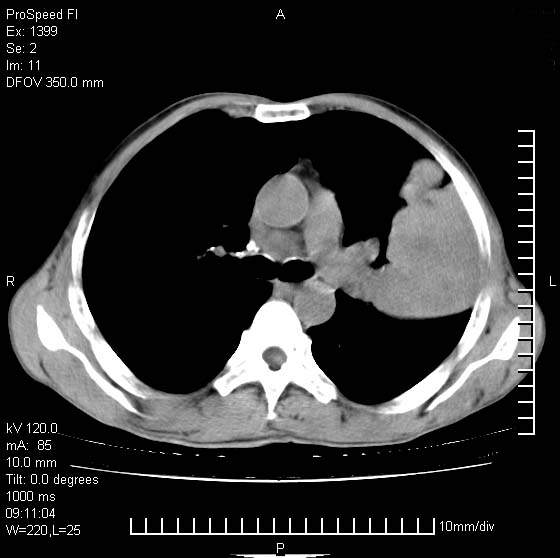

以下是引用卜一在2007-1-19 9:55:00的发言:[br]左肺沿胸膜下巨大肿块影,边缘呈分叶征,纵隔内见肿大淋巴结,右肺内另见一不规则结节影 .考虑:左肺周围性肺癌伴纵隔 右肺内转移.